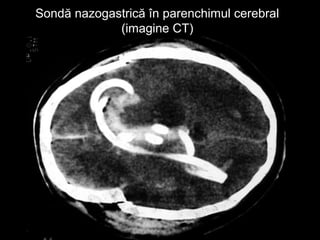

 Sondă de aspiraţie

gastrică introdusă

pe cale nazală –

manevră interzisă

Sondă nazogastrică în parenchimul cerebralSondă nazogastrică în parenchimul cerebral

(imagine CT)(imagine CT)

Hematoame periorbitaleHematoame periorbitale “Ochi de panda” – sugestivi pentru fractura de bază de craniu  Sondă de aspiraţie gastrică introdusă pe cale nazală – manevră interzisă

Sondă nazogastrică înparenchimul cerebralSondă nazogastrică în parenchimul cerebral (imagine CT)(imagine CT)